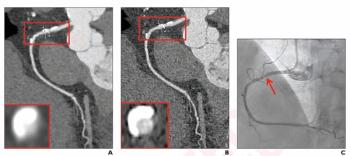

Study Reveals Significant Prevalence of Abnormal PET/MRI and Dual-Energy CT Findings with Long Covid

In a prospective study involving nearly 100 patients with Long Covid, 57 percent of patients had PET/MRI abnormalities and 90 percent of the cohort had abnormalities on dual-energy CT scans.